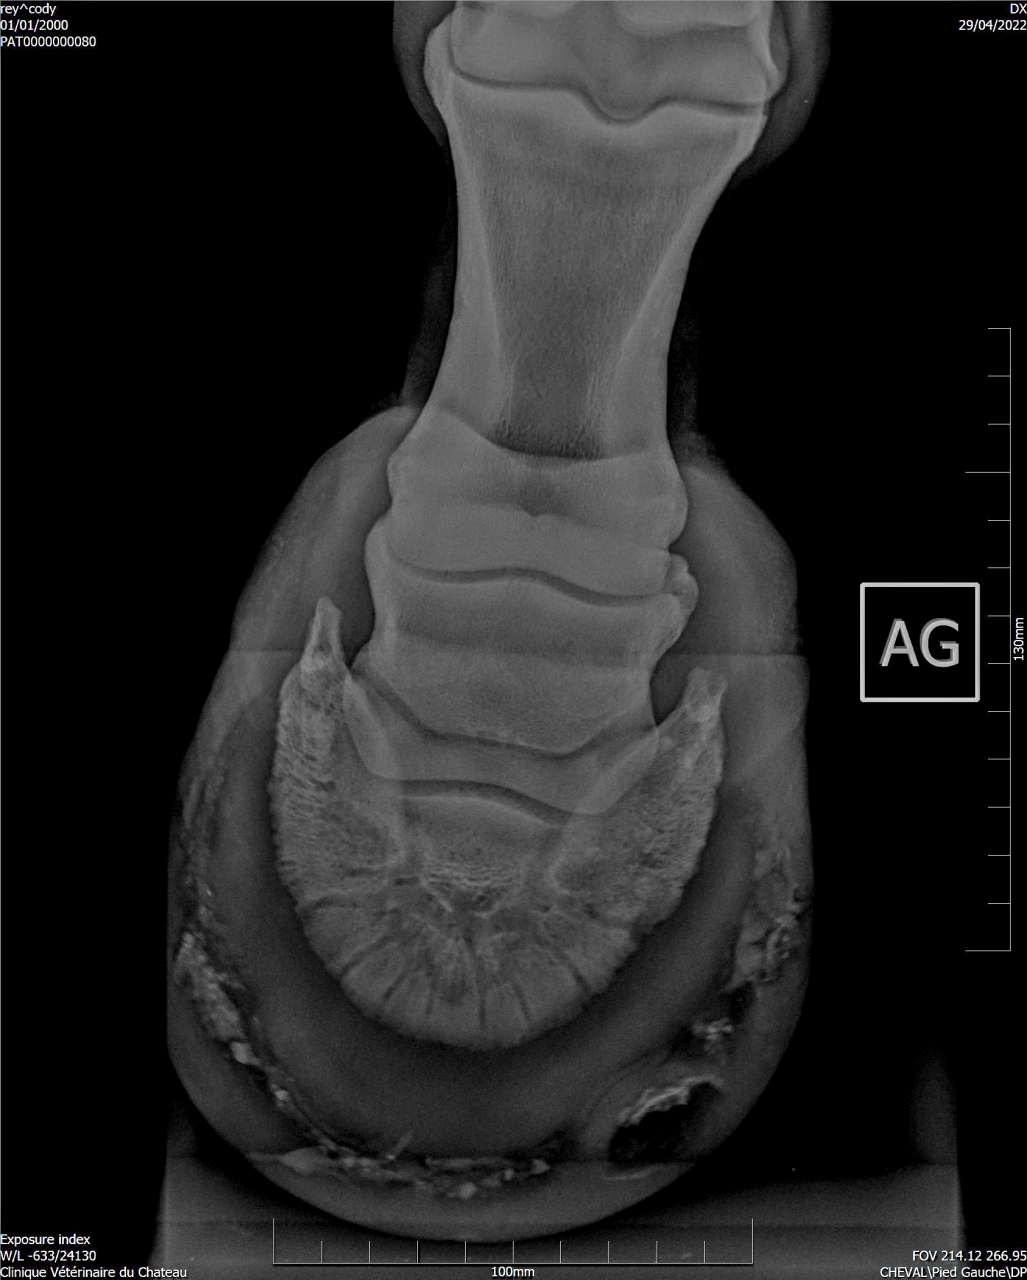

| Dire merci | Suite aux radios faites sur Cody, j'ai fait passer un véto spécialisé en boiteries. Examen : AG paturon légèrement déformé (je n’avais jamais remarqué) Pince + Fers avec oignons et plaques Planche négative (apparemment Cody a bien réagi) Flexions statiques normales Légère irrégularité ADT à main dte (effectivement pas trop mal, ça a été pire) Radiographies fournies : Légère ossification processus palmaires (moi je ne vois rien de particulier sur les radios) Légère arthrose interphalangienne proximale (idem) 1 à 3 fossettes sur chaque naviculaire (apparemment pas catastrophique, le véto m’a montré d’autres radios de chevaux naviculaires pour comparer) Recommandations : Marechalerie : poursuivre à l’identique (Oignons et plaques) Traitement : Dextropine et Navitol Voici les radios : ![]() ![]() ![]() ![]() Si quelqu'un pouvait m’expliquer en termes simples ![]() |

| Dire merci | Je suis pas experte en lecture de radios, loin de là, mais le bord distal du naviculaire semble quand même largement plus vilain que les cartilages palmaires ? Et ça sur les deux pieds.Je serai par contre curieuse de voir des photos du parage vu ce qu’on voit aux radios.. Message édité le 01/07/22 à 22:45 |

DéconnectéDire merci | fourmilières impressionnantes et pieds vraiment salement pas parés. La sensibilité aurait pu être amortie avec des hipposandales et les pieds soignés correctement et fréquemment par un pareur qualifié. |

| Dire merci | Honnêtement j'ai vu bien pire en ossification des processus palmaires, il faut que je retrouve les radios. Pour le reste je rejoins les autres les pieds sont beaucoup beaucoup trop longs. |

| Dire merci | Je pense qu’un cheval sur deux aura les cartilages plus calcifiés que celui là Peut être même plus… Son plus gros soucis sur les radios c’est quand même l’entretien des pieds. Et c’est le seul facteur sur lequel on peut jouer et qui n’est pas irréversible Faire un parage coûte moins cher que 2 paires de radios |